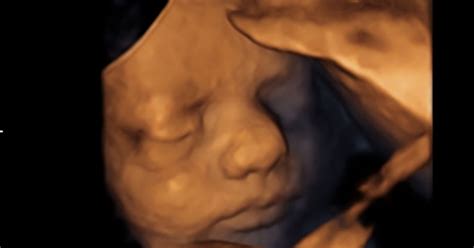

Razvoj Dojenčka v 15. Tednu

V 15. tednu nosečnosti je otrokova koža še vedno tanka in prosojna, kar omogoča celo opazovanje žil. Kožo prekrivajo drobne dlačice, imenovane lanugo, ob vsaki od teh dlačic pa se nahaja žleza lojnica, ki proizvaja sirasto maz, znano kot vernix caseosa. Ta snov ščiti nežno kožo dojenčka pred amnijsko tekočino. Pomembna novost je, da se začne dvigovati in spuščati dojenčkov toraks, kar predstavlja začetek dihalnih gibov, čeprav so ti še nepravilni. Morda prav ta mehanizem omogoča vohalnemu sistemu, da začne "vohati" okolje, poganjano z aromatičnimi molekulami v amnijski tekočini.